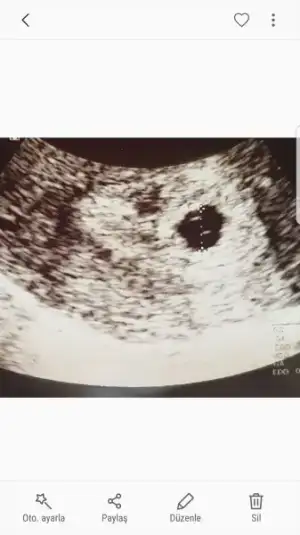

Normal cnm endiselenme karindan daha gec gorunur alttan daha cabukgorunurkızlar merhaba. ben bugün karından muayene oldum doktorun ultrasonuna göre 6+0 günlük çıktı kesem. ama bebeği henüz göremedi doktor. bu normal mi??

kızlar merhaba. ben bugün karından muayene oldum doktorun ultrasonuna göre 6+0 günlük çıktı kesem. ama bebeği henüz göremedi doktor. bu normal mi??

Normal cnm endiselenme karindan daha gec gorunur alttan daha cabukgorunur

bu haftalarda vajinal muayene ile görülürmüş, normal yani

Benim kese beş haftalıkken göründü.kızlar merhaba. ben bugün karından muayene oldum doktorun ultrasonuna göre 6+0 günlük çıktı kesem. ama bebeği henüz göremedi doktor. bu normal mi??

masallah canım. ben 5+3 te keseyi gördüm. ama benim ki erken döllenme. yani normalde 6+0 gibiyken gördüm diye düsünebilirsin. fakat doktorum alttan muayene ile bakmisti. kesenin icinde bir de yolk sac olması gerekiyormuş. onu da gördügü zaman doktor bu gebelik boş gebelik degil yorumunu yapabiliyor. yolk kesesi de var miydı içinde? bak 5+3 usg mi paylasıyorum. kesenin icinde 2 tane nokta goreceksin, o yolk kesesinin iki kenariymış.kızlar merhaba. ben bugün karından muayene oldum doktorun ultrasonuna göre 6+0 günlük çıktı kesem. ama bebeği henüz göremedi doktor. bu normal mi??